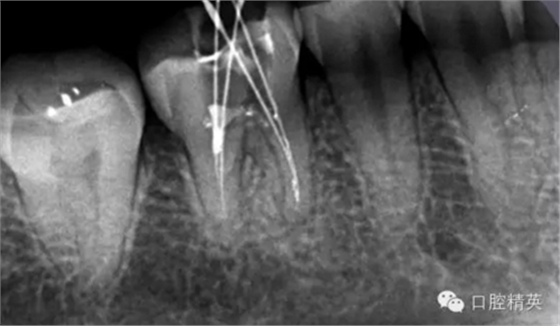

這個病例是我準備分根的病例,保留近中根,曾在外院做過干尸長達數(shù)十年。8號挫疏通時近舌根堵,近頰未找到。在這個病例中首先要知道是為什么根管難以疏通,首先是長時間的干尸,和患者年紀較大根管逐漸變窄,根管道路可能會出現(xiàn)堵塞,在這張病例中我能知道的是稍有不慎就會形成臺階,從而導致根管堵塞加重,更加難以疏通。

近舌8號k挫疏通,根尖部彎曲,我花費時間2小時疏通。我個人覺得根管能否被疏通,第一個重要因素是時間,因為作為牙體牙髓的醫(yī)生,首先就是需要的就是耐心。我個人覺得耐心是非常重要,因為很多根管被疏通時,都是我們快要放棄的時候。所以我每次都會安慰自己快好了,快好了,就差一點點,在堅持一會兒就好了。可以說沒有耐心,想做好牙體牙髓,我個人覺得很難很難。第二個就是手法,不知道大家啟用挫是什么挫,一般我個人認為,最好從8號開始疏通,這樣不容易在狹窄的根管內(nèi)形成臺階(如果有條件的可以從6號開始)。

這個病例難以疏通在于根中上段堵塞,根尖下段有臺階的形成,感覺不到彎曲的方向。首先我們處理根上段,我們可以采取的方法是先預備跟中上段,將它擴開來,這樣有利于根尖下段的預備,建立良好的視野。對于根尖下段的臺階和彎曲 ,8號挫預彎,第二步要知道根管彎曲的方向,沿著根管彎曲的方向疏通。特別是有臺階的地方,一定不要硬來,慢慢旋轉(zhuǎn)找到根管彎曲的方向(結(jié)合x線片)避開臺階,一定要記住慢慢旋轉(zhuǎn)角度越小越好,正旋逆旋找“緊點”,有經(jīng)驗的醫(yī)生大概都知道,找到了“緊點”就等于找到了希望。手法一定要輕柔不易暴力!切記切記!戒浮戒躁(這句話也是特別要告訴我自己)。

近頰為疏通。慢慢找點可下,近頰花費一小時。

近中兩根試尖,預備根管15分鐘。

近中兩根根充。

這個病例主要是針對臺階的疏通方法,感覺好像很抽象很飄渺。因為這些都是要看自己的手感和很多細節(jié)的注意。特別是旋轉(zhuǎn)的角度不宜過大,一點一點的找可以避開臺階的道路。